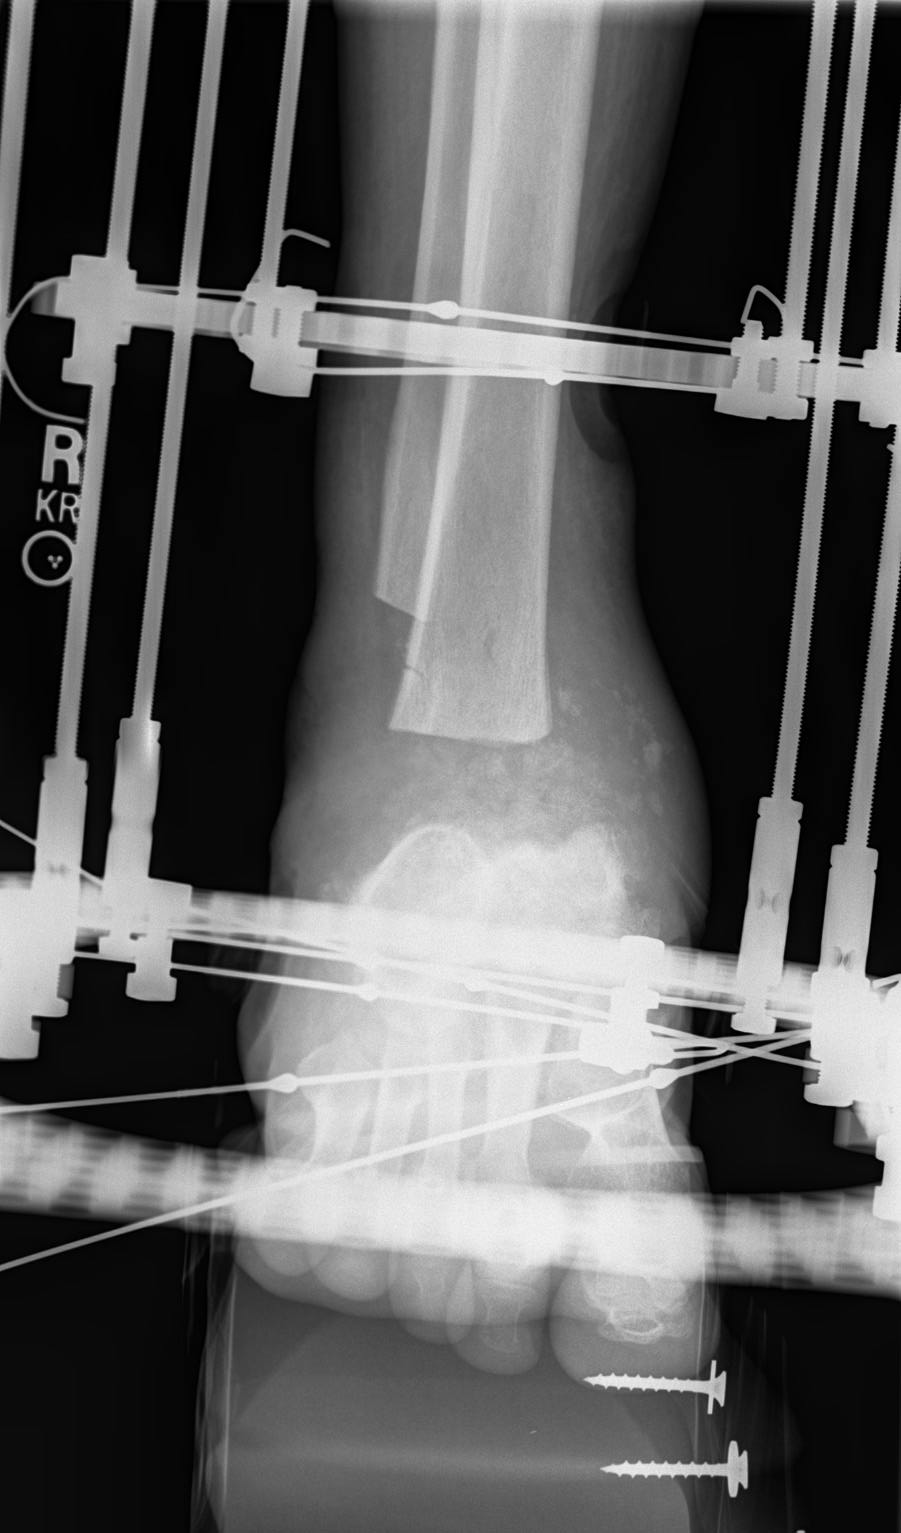

Nonunion: Ankle Case 2

Treatment in ProgressThese x-rays show treatment in progress after removal of bone and tissue at the nonunion site. Treatment consists of Ilizarov bone transport and compression to move a segment of bone downward to obtain fusion of the ankle joint. |